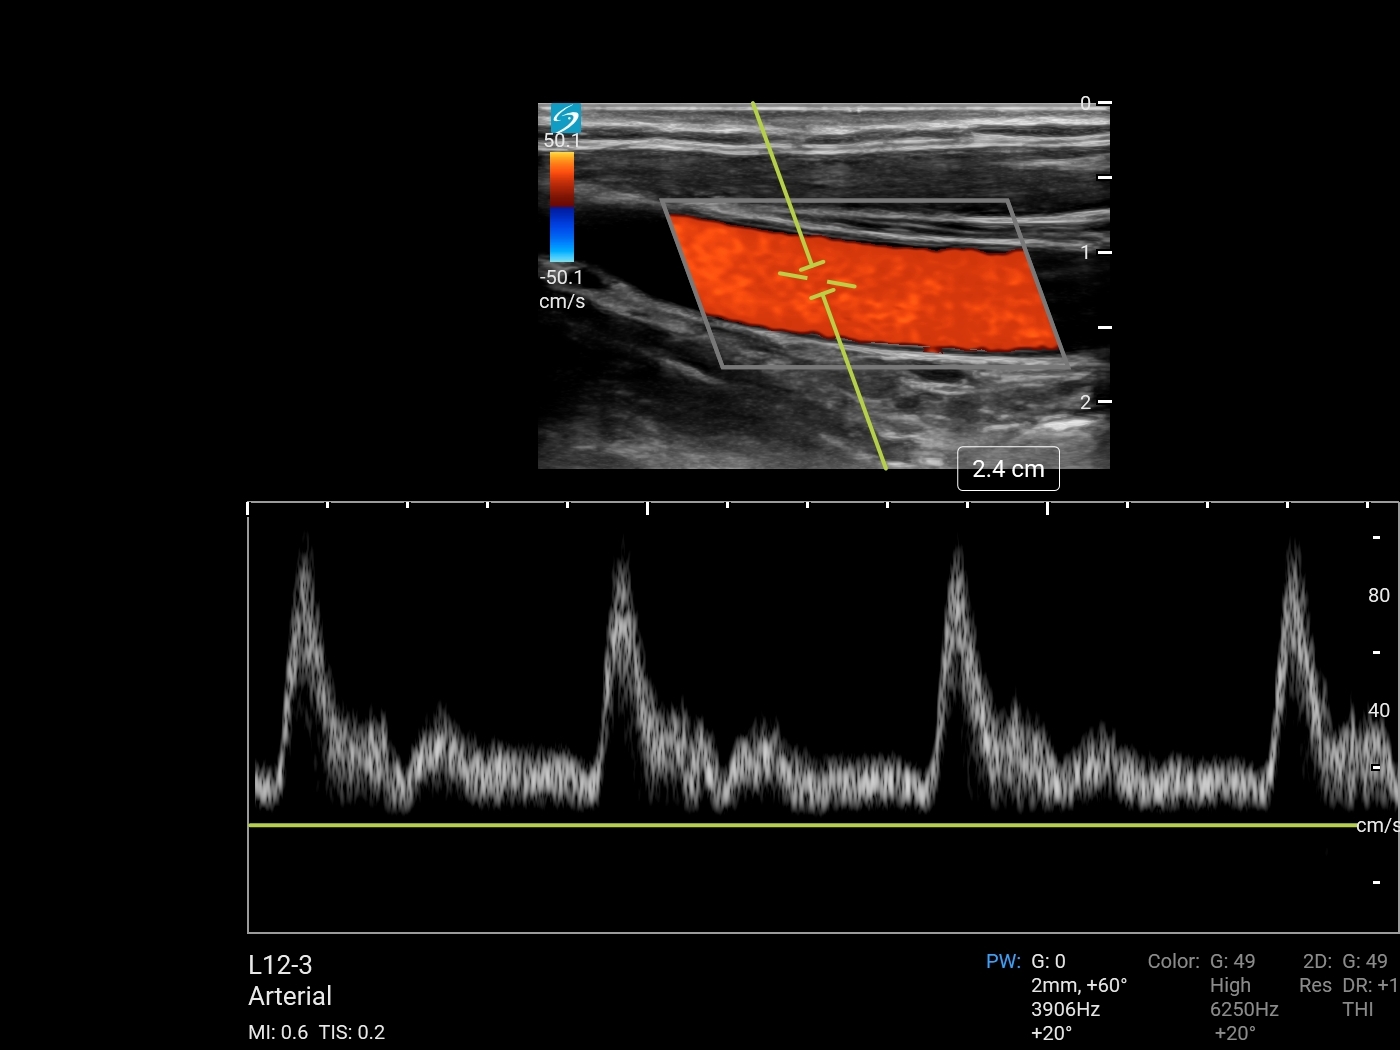

颈动脉颈总动脉 (CCA) 多普勒图像